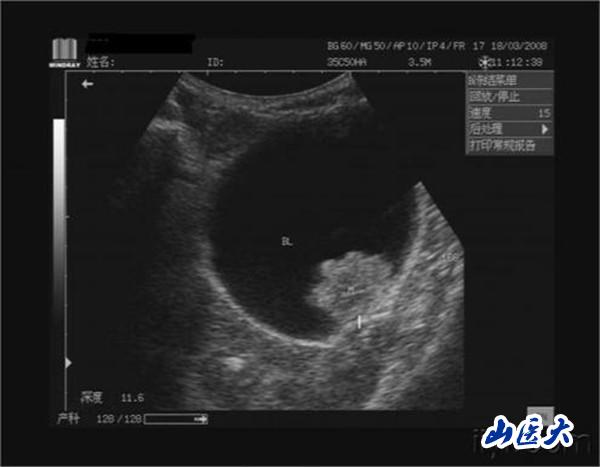

膀胱腫瘤是泌尿系統中最常見的腫瘤,多數為移行上皮細胞癌,在膀胱側壁及后壁最多,其次為三角區和頂部。在國外,膀胱腫瘤的發病率在男性泌尿生殖器腫瘤中僅次于前列腺癌,居第2位,在國內則占首位。男性發病率為女性的3~4倍,年齡以50~70歲為多。非肌層浸潤膀胱腫瘤(淺表性膀胱癌)占初發膀胱腫瘤的70%,治療方法主要是手術切除。

血尿為膀胱癌最常見的首發癥狀,85%的患者可出現反復發作的無痛性間歇性肉眼血尿,出血量可多可少,嚴重時帶有血塊,在膀胱癌發病的全過程100%或早或晚出現血尿。